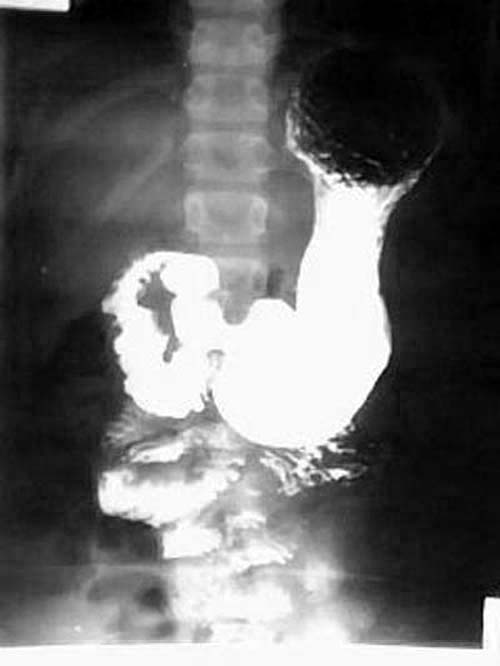

女性,12岁,因腹痛,恶心呕吐一周,腹呈绞痛,痛时可扪及包块,呕吐物为胆汁.大便不成形.于外院输液无好转(具体不详),遂转入我院,经对症治疗3天后好转,

以下是服钡后立位摄片:]

ped0661结果:中肠旋转不良伴中肠扭转.为手术所证实

本例是典型的中肠旋转不良伴中肠扭转的病例.为手术所证实.

本例临床表现是上消化道梗阻的表现.但初入院时外科诊断并不明确.透视未见明显异常(其他医生作的,具体不详),两次超声均未能明确诊断.入院后行禁食,胃肠减压,对症,输液等处理,约3天后腹痛缓解.拔胃管的当天吃了二个小包子,第二天作钡餐,钡餐示:十二指肠水平段不全梗阻(腹膜带压迫),空肠在左上腹小段盘曲后随即转向右,并于中腹部呈螺旋形下降(这是中肠旋转不良伴中肠扭转的典型表现),大部份回肠位于左下腹.因外科开的是上消化道钡餐,我已经把大部份小肠都看了,又到了下班时间,就没有继续往下追踪,如果断续追踪发现盲肠的位置异常,则可进一步的证实和肯定诊断.

中肠的旋转不良合并扭转在术前是可以确诊的,肠旋转不良作钡餐时不时可以见到,但合并扭转的并不多。根据本人体会及结合文献,中肠的旋转不良合并扭转,可以没有肠梗阻,但也可以有梗阻,甚至绞窄,坏死。几年前我也遇见过一位成人的小肠旋转不良伴扭转的病例.患者大约四、五十岁.没有明显肠梗阻,(遗憾的是胶片已销毁,不然可请老师们鉴别一下)。但不论有无梗阻,一旦发现有扭转均为手术指征。

钡餐检查可获得肠旋转不良的全部信息,包括十二指肠有无梗阻、十二指肠空肠曲位置、有无肠扭转及回盲部位置,是诊断本病的首选方法。钡灌肠造影发现回盲部在左腹部或右上腹部,可确诊肠旋转不良,但不能诊断是否并发中肠扭转。